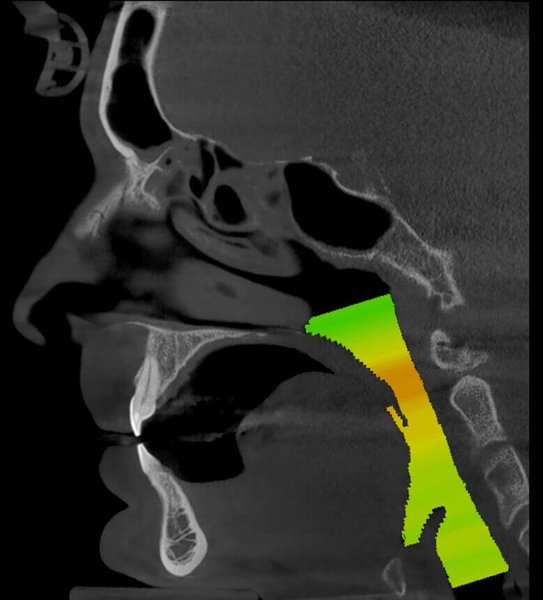

GIANO HR – универсальное обновляемое устройство от NewTom для всех задач, связанных с радиографией. Благодаря полному диапазону опций 2D и 3D исследования для стоматологии оно предлагает множество особых трехмерных обследований для челюстно-лицевой хирургии, оториноларингологии и осмотра шейного отдела позвоночника. Визуализация только наивысшего качества с технологиями и опытом NewTom

NNT – программное обеспечение NewTom, предоставляющее несколько специальных режимов применения для имплантологии, эндодонтии, пародонтологии, челюстно-лицевой хирургии и радиографии. Это мощное технологически новейшее устройство, разработанное, чтобы снимать и обрабатывать изображения в несколько простых шагов для получения информации, необходимой для конкретного подробного диагноза пациенту. Продвинутое устройство, дающее врачу специальные инструменты для измерения анатомической области (расстояния и углы), нахождения нижнего альвеолярного нерва и замера объема верхних дыхательных путей.

NewTom GiANO HR новейшая модель была официально представлена на международном конгрессе радиологов ECR 2018 в марте в Вене. Благодаря обновленным системам механики и запатентованным механизмам работы аппарат отличается от своих сверстников Высочайшим качеством получаемых изображений, как 2D, так и 3D. Лучшее качество снимков и мы отвечаем за это! Этот аппарат заменит три аппарата! Панорамный аппарат, цефалометрическая приставка и конусно-лучевая компьютерная томография интегрированы в единую платформу. В комплекте детектор для выполнения 3D исследований с захватом области 13х16 см, Сьемный 2D CMOS детектор для выполнения панорамных исследований, и ТРГ.